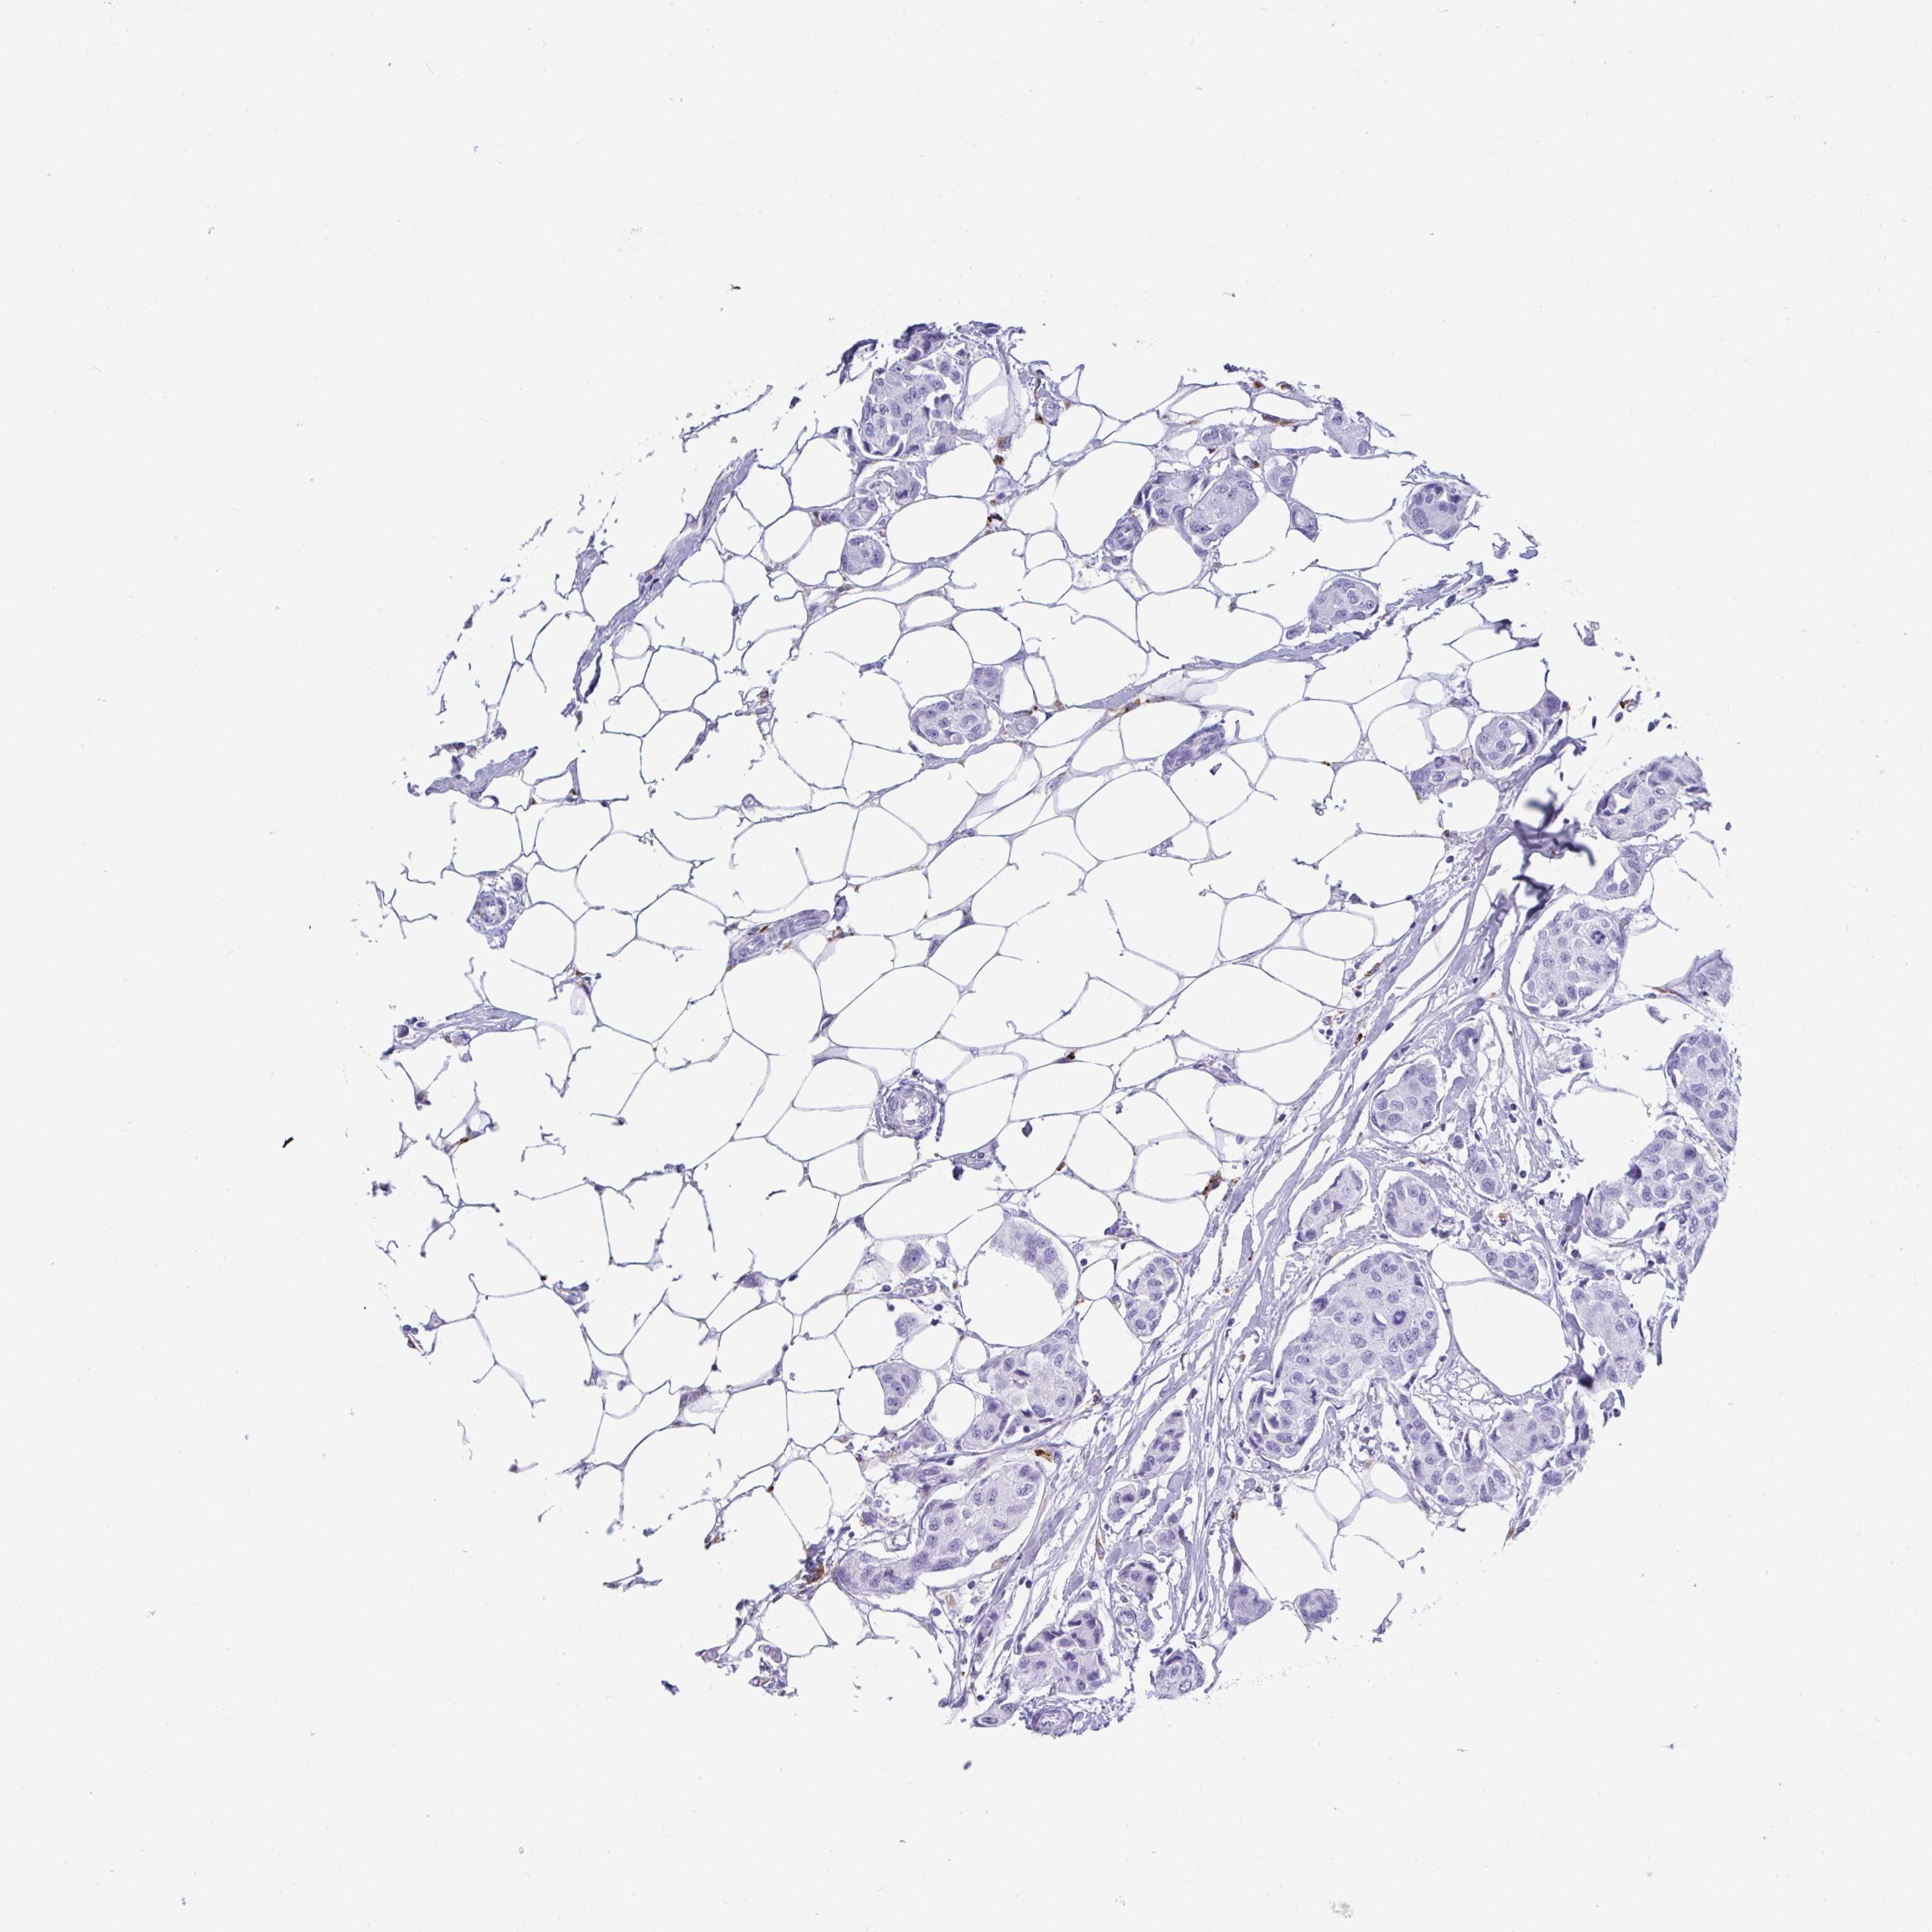

CANCER BREAST CANCER Show tissue menu

BRCA TCGA BRCA VALIDATION PROTEIN EXPRESSION